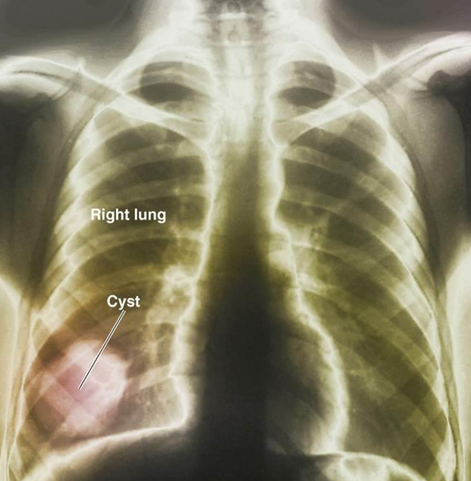

Hydatid Disease (helminthic)

Pathogen → Echinococcus granulosus

Symptoms → Larvae form in body; may be very large and cause damage

Reservoir → Intermediate host: sheep, humans

Definitive host: dogs

Diagnostic test → Serology; X-ray exam

Treatment → Surgical removal; albendazole

*Develops a hydatid cyst that can grow and hold up to 15 liters of fluid; May rupture, causing anaphylactic shock